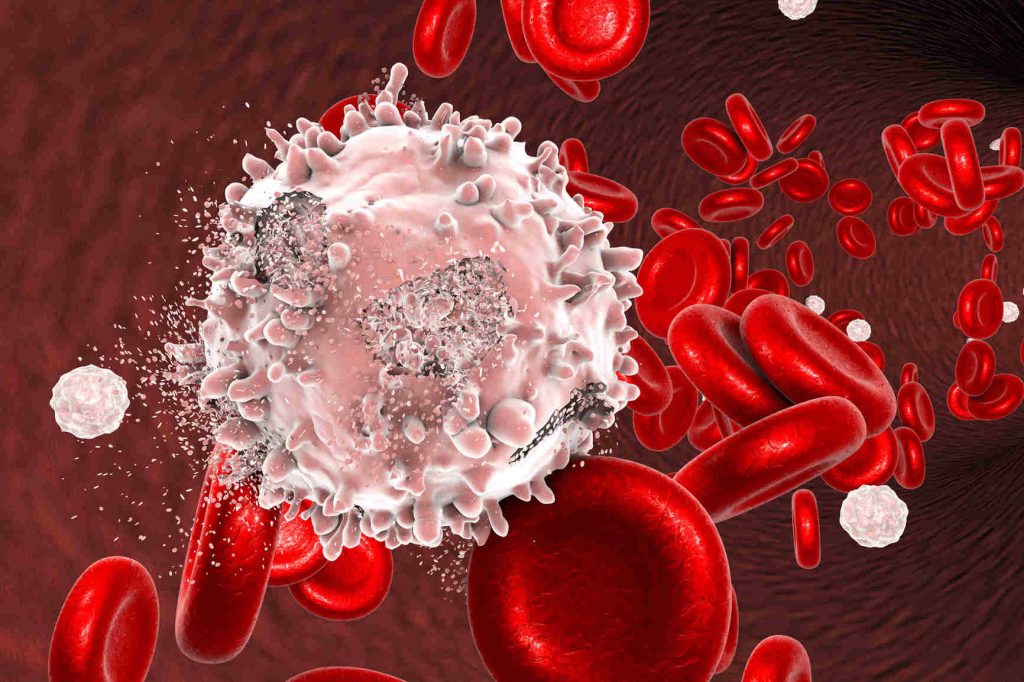

Καρκίνος